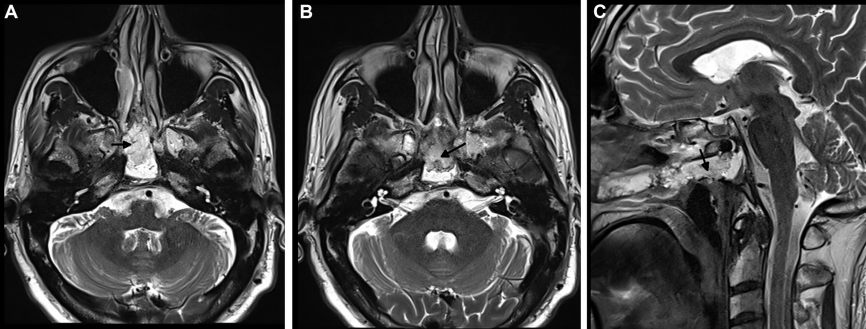

最终手术顺利完成,术后 MRI 证实肿瘤被完全切除(箭头所指为填充的脂肪),同时鼻窝保持完整。在2个月的随访中,内镜检查没有发现结痂,患者也没有抱怨任何鼻腔不适。

通过单鼻孔入路,福教授为Roger成功完成了手术,术后MRI显示肿瘤被完全切除。术中同样采用了鼻粘膜修复技术,保证了术后的生活质量。

术后MRI影像明确肿瘤全切情况,以及用于重建的自体脂肪